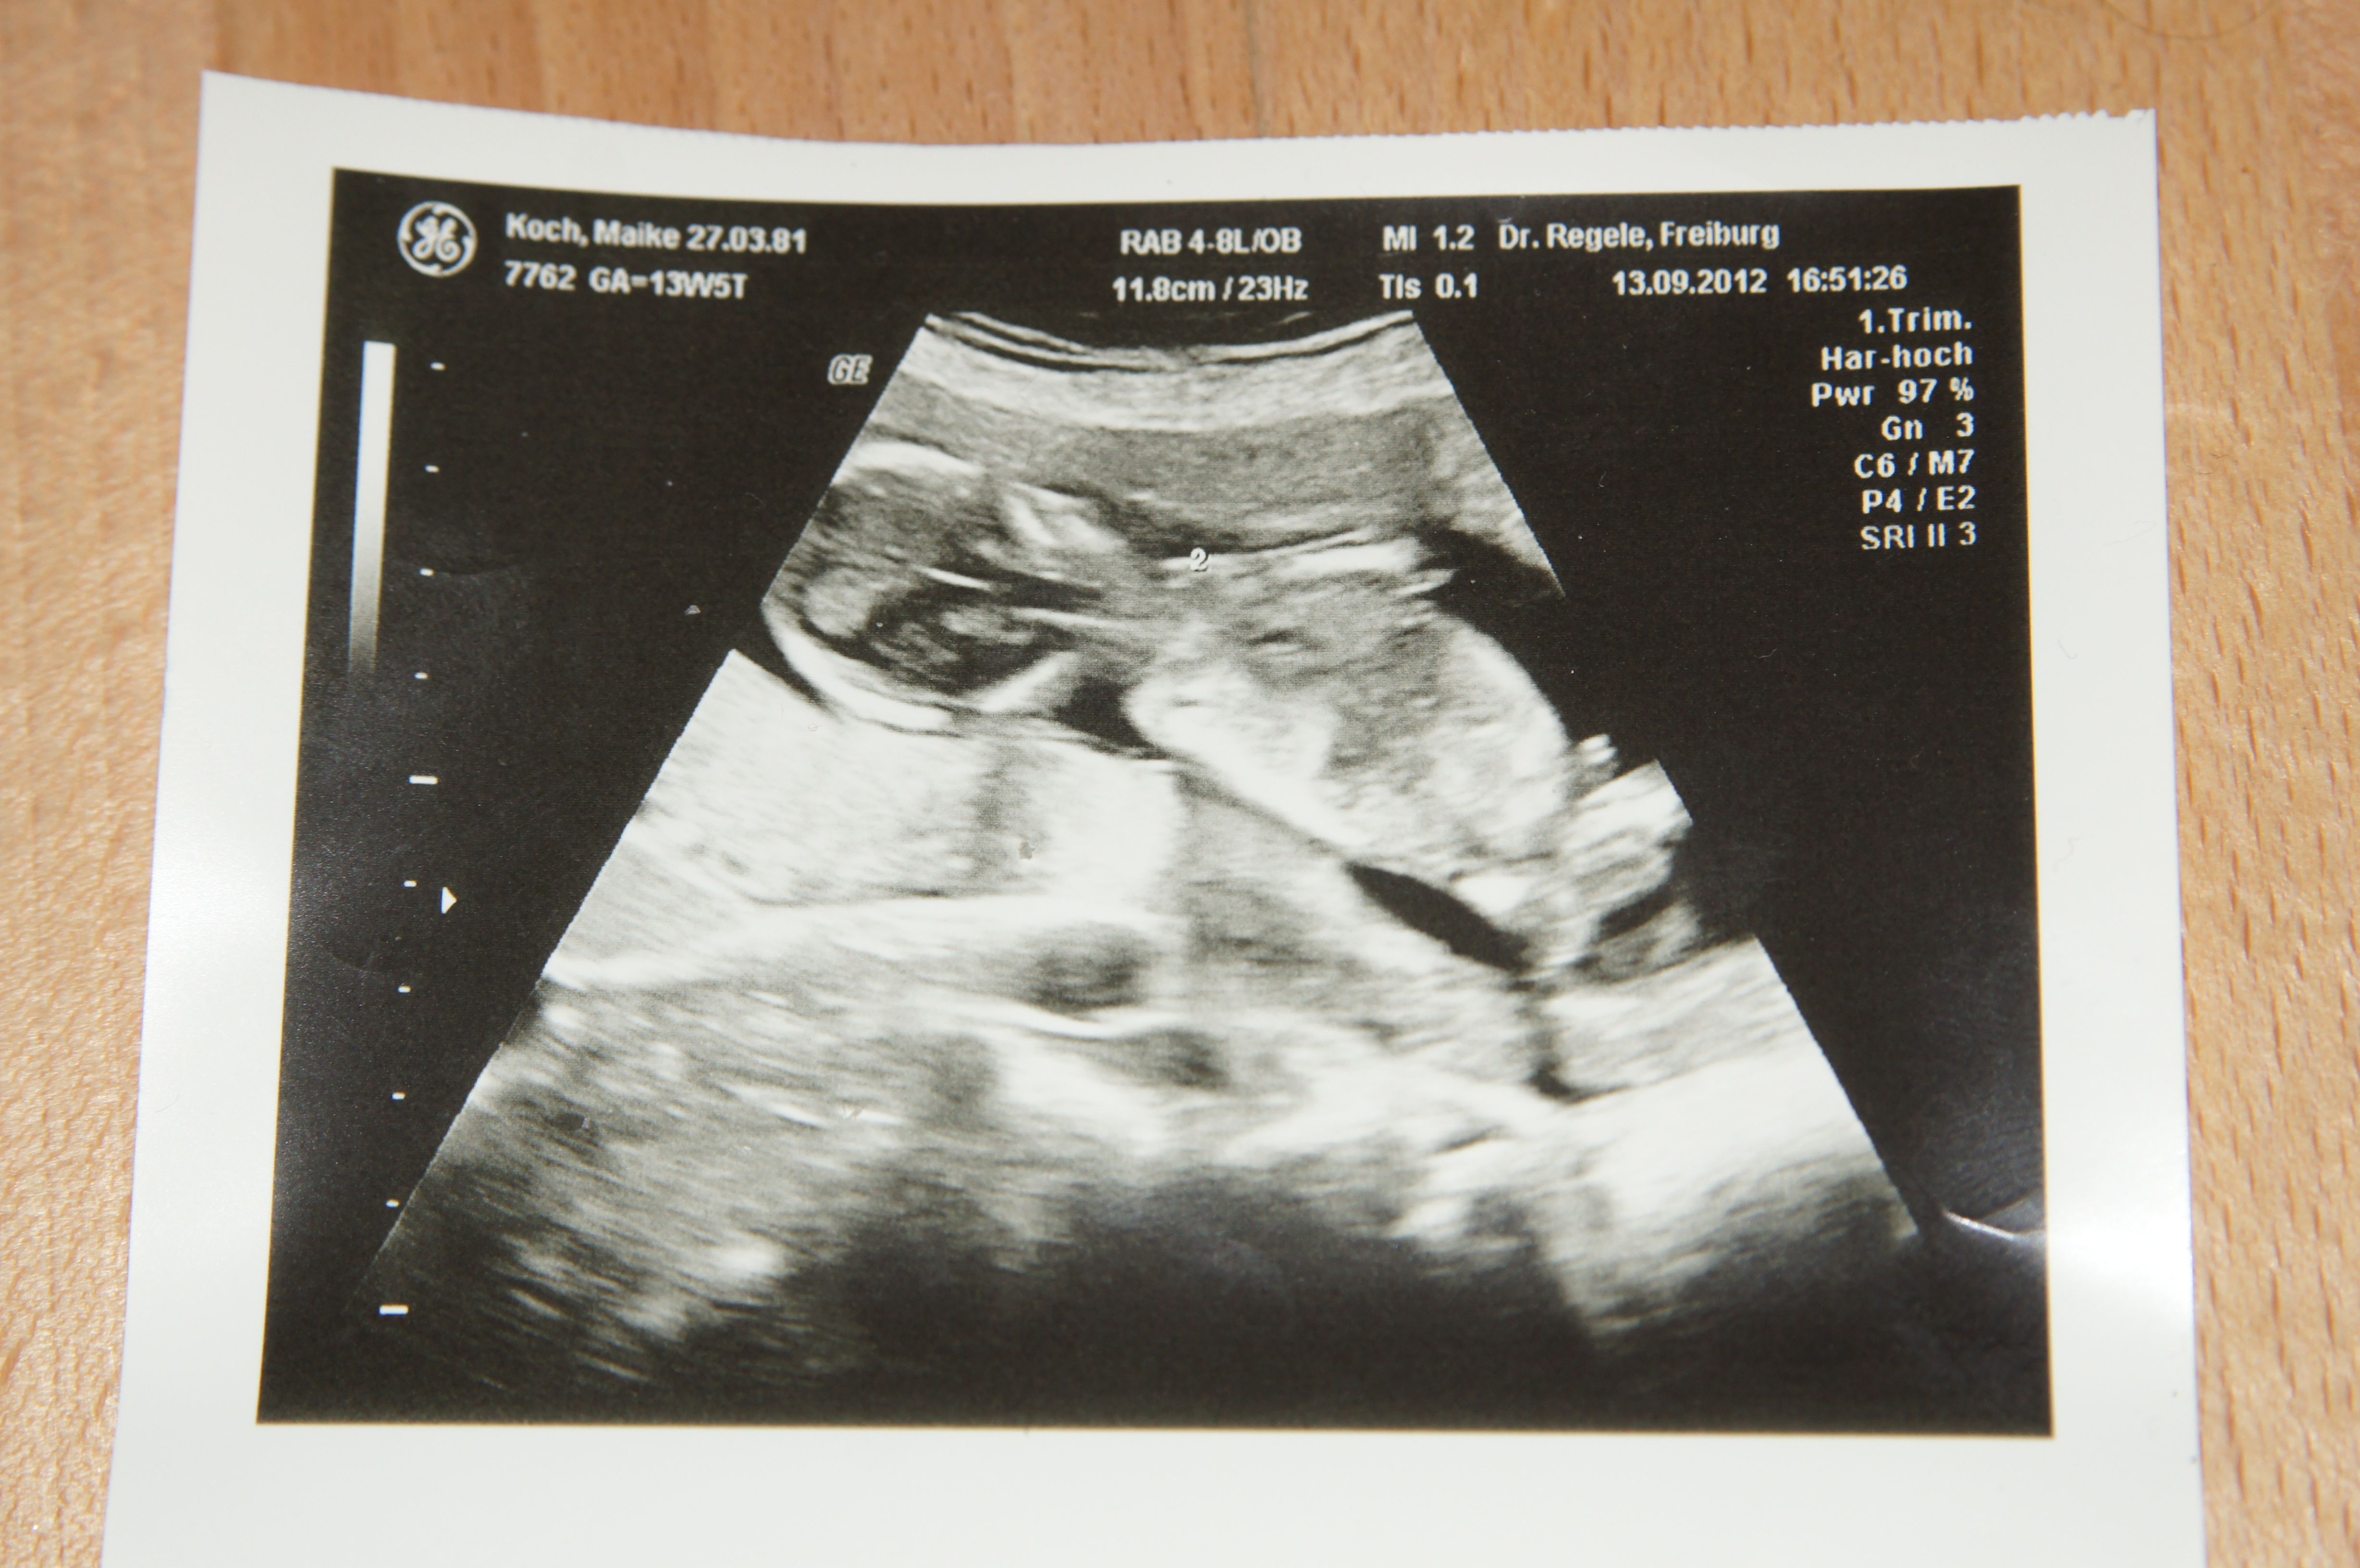

I am not sure baby is in a good position. I don't see anything. Sorry I'm not an expert though. Congrats